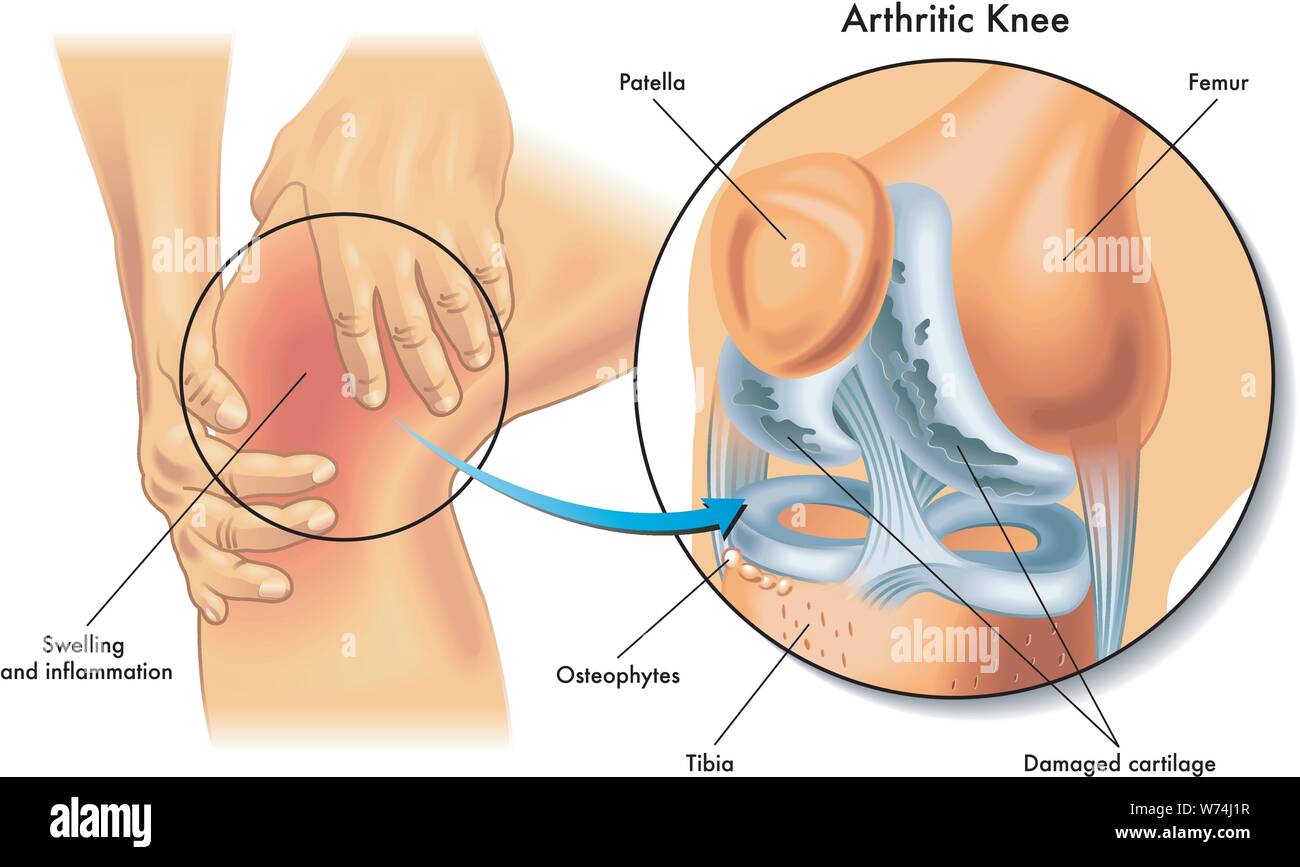

Medical illustration of the symptoms of arthritic knee Stock Vectorhttps://www.alamy.com/image-license-details/?v=1https://www.alamy.com/medical-illustration-of-the-symptoms-of-arthritic-knee-image262560083.html

Medical illustration of the symptoms of arthritic knee Stock Vectorhttps://www.alamy.com/image-license-details/?v=1https://www.alamy.com/medical-illustration-of-the-symptoms-of-arthritic-knee-image262560083.htmlRFW74J1R–Medical illustration of the symptoms of arthritic knee